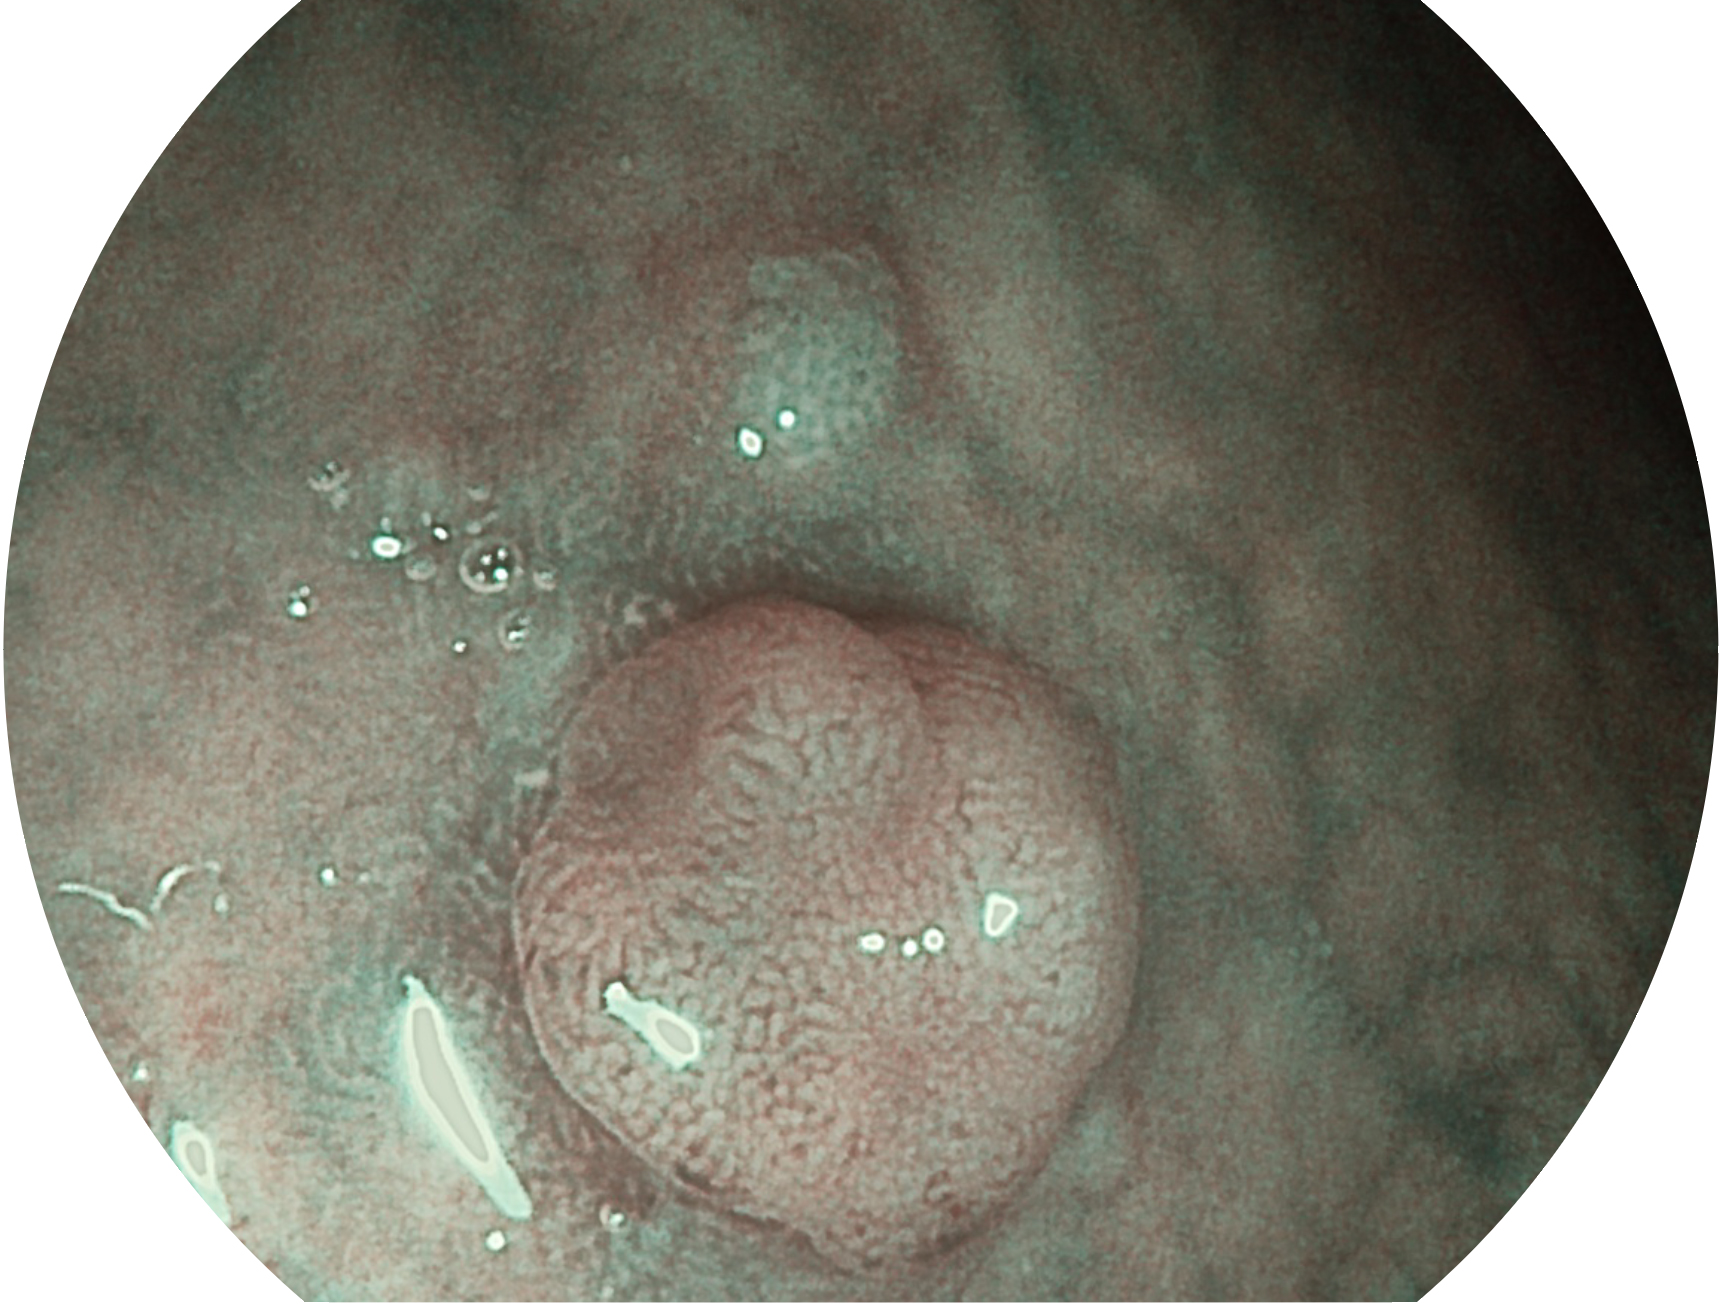

亚星官网新开发的内镜染色技术,主要是基于多波长LED 光源的开发,VLS-55Q 四波长LED 光源是由四个不同颜色的LED光按照相应照明模式所规定的特定发光比例进行合束后形成,合束后形成的照明光的光谱由红光、绿光、蓝光及蓝紫光这四个不同的波段范围构成。具有更高光谱自由度,通过光谱比例的控制,实现了聚谱成像技术,英文全称为“Spectral Focused Imaging, SFI”,缩写为“SFI”和光电复合染色成像技术,英文全称为“Versatile Intelligent Staining Technology, VIST”,缩写为“VIST”。